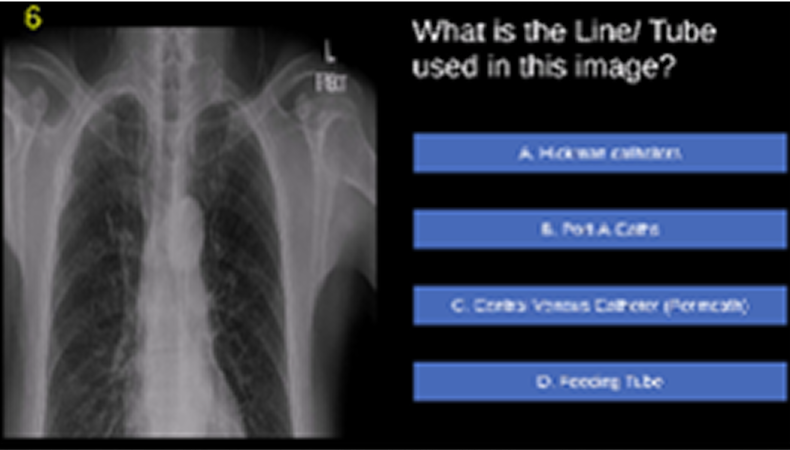

Minigame 6

Identifying the type of line or tube used in a given CXR